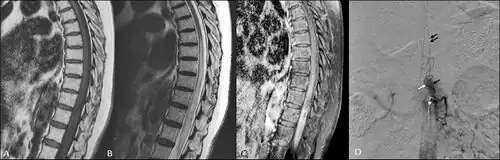

| T2 weighted MRI showing an arteriovenous malformation indicated by the cursor | |

Foix–Alajouanine syndrome, also called subacute ascending necrotizing myelitis,[1] is a disease caused by an arteriovenous malformation of the spinal cord.[2] In particular, most cases involve dural arteriovenous malformations that present in the lower thoracic or lumbar spinal cord. The condition is named after Charles Foix and Théophile Alajouanine who first described the condition in 1926.[3][4]

Clinically, the patient may present with neurological symptoms such as numbness, weakness, loss of reflexes, or even sudden or progressive paralysis.[6] The affected portion of the body will correlate to where the lesion lies within the spinal cord. The disease typically has an insidious onset, but symptoms may manifest suddenly. A thorough physical exam may lead a physician toward targeted imaging, with MRI being the most appropriate imaging modality for initial diagnosis. A spinal MRA will serve as a superior imaging technique to visualize the extent of the arteriovenous malformation within the cord and may be especially useful if surgical treatment is attempted.[7]